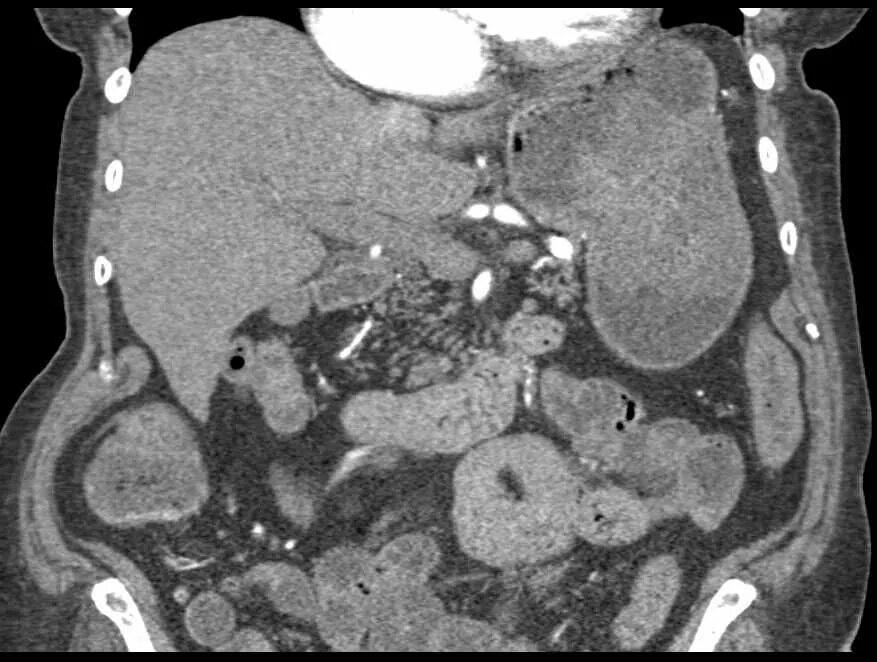

Язва желудка кт